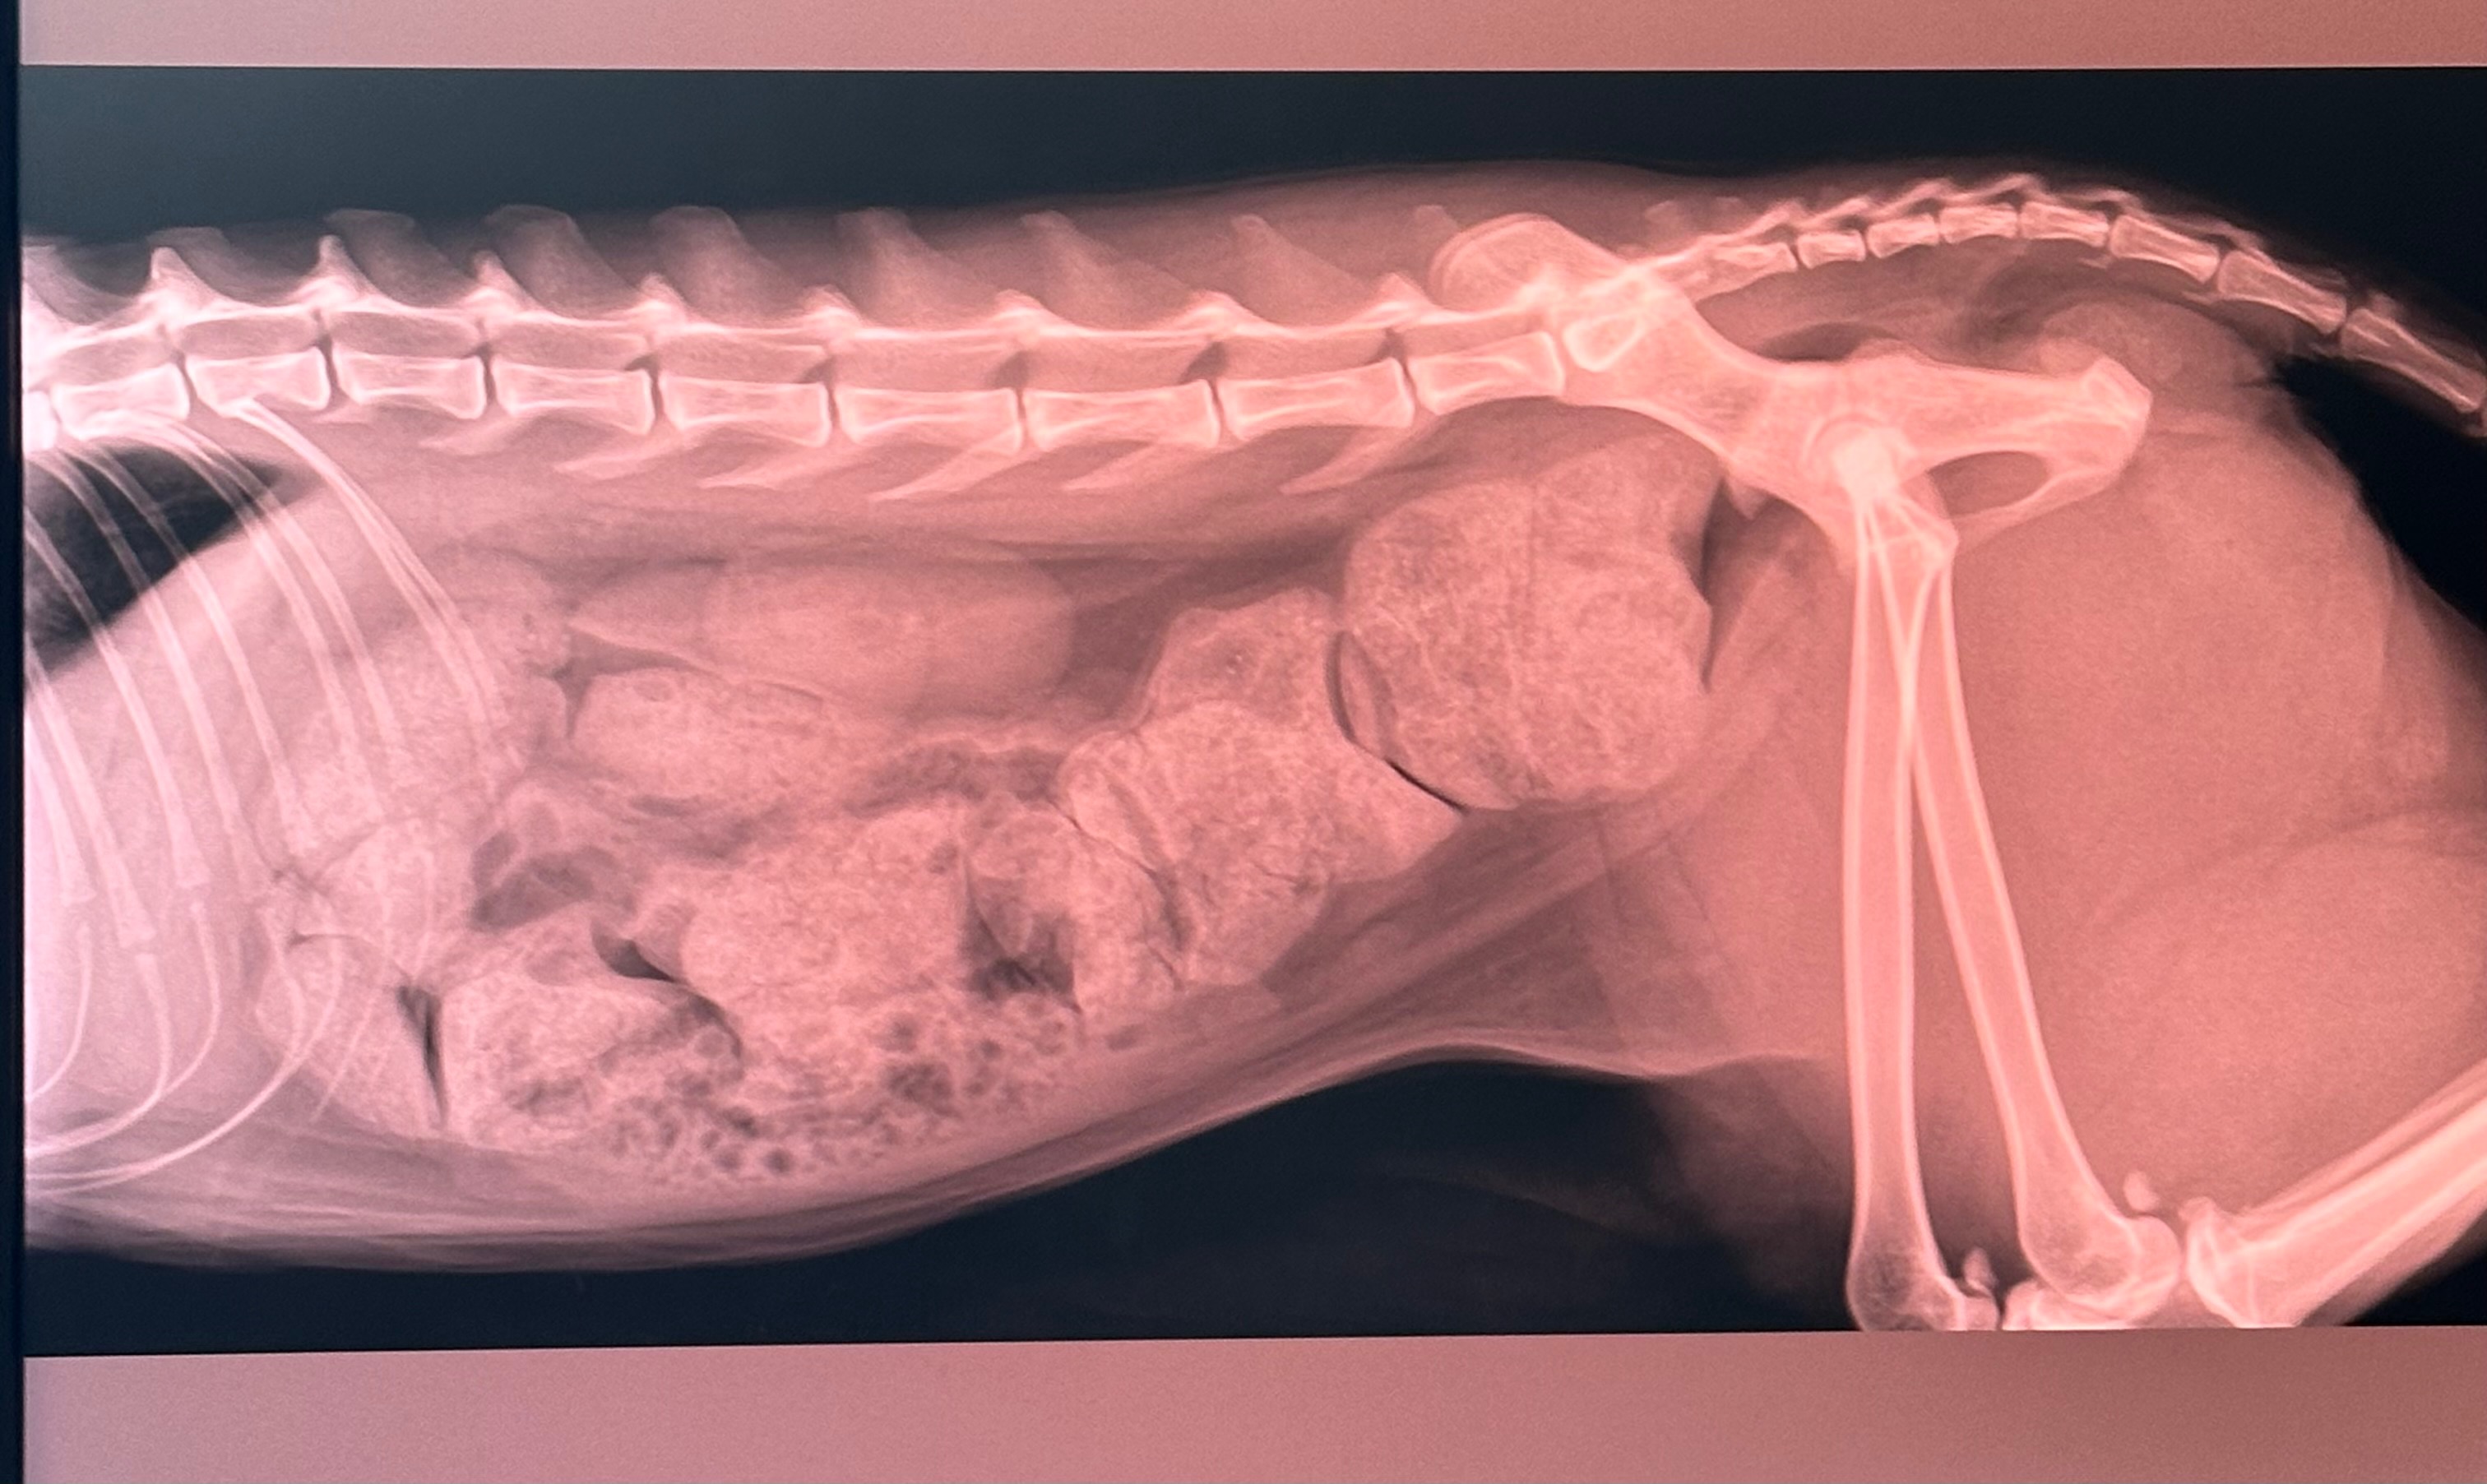

Turns out it is megacolon. In short, he is so backed up and his poop is so large he cannot physically pass it on his own.

He is currently being treated to remove the current stool backup (picture attached), which is a long, extensive, and expensive process.